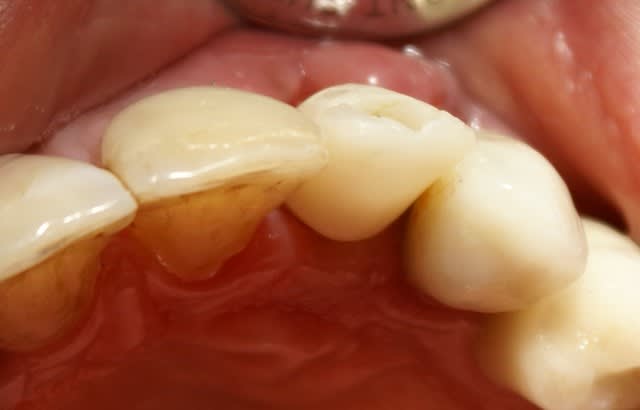

Dans ce cas là, c'était une implantation post extractionnelle immédiate et une mise en esthétique immediate.

Pour ceramik, l'implant est un Xive 3.8 dans le premier cas et un 3.4 dans le second (peut être un peu sous-dimentionné d'ailleurs).

Tout à fait d'accord growler et c'est d'ailleurs ce que l'on peut voir sur le cas suivant. Fracture radiculaire, aucune infection periradicualire. Extraction et implantation immediate. Espace existant entre l'implant et l'alvéole est comblé par du BioOss. Un logement sous gingival est formé en vestibulaire et palatin de facon à pouvoir recouvrir le tout par BioGide et un conjonctif enfoui.

L'implant est de 15mm mais l'alvéole était large et 50% environ de la surface implantaire n'était en contact qu'avec du BioOss. J'ai pour cela préféré enfouir.